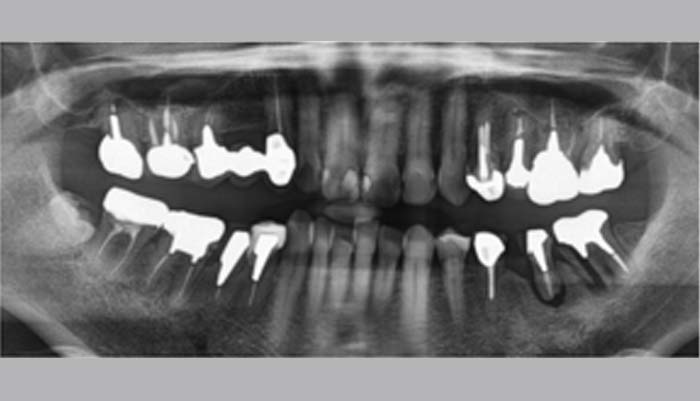

症例紹介